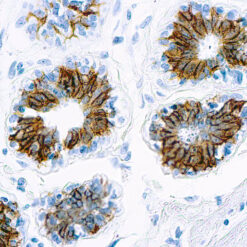

Synaptophysin (SYP02)

This antibody isspecific to a 38 kDa protein. Synaptophysin is an glycoprotein occurring in presynaptic vesicles of neurons in the brain, spinal cord, retina, vesicles of adrenal medulla and in neuromuscular junctions. This antibody reacts with neuroendocrine neoplasms of neural as well as epithelial types.

| Positive Control Tissue | Pancreas |